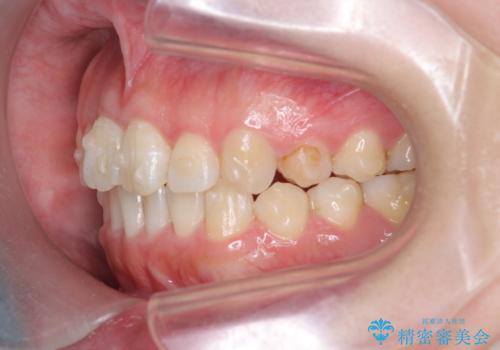

歯並びが改善したとともに、骨隆起を除去したことで舌をしまうスペースも増え安定した口腔内環境を確立することができました。